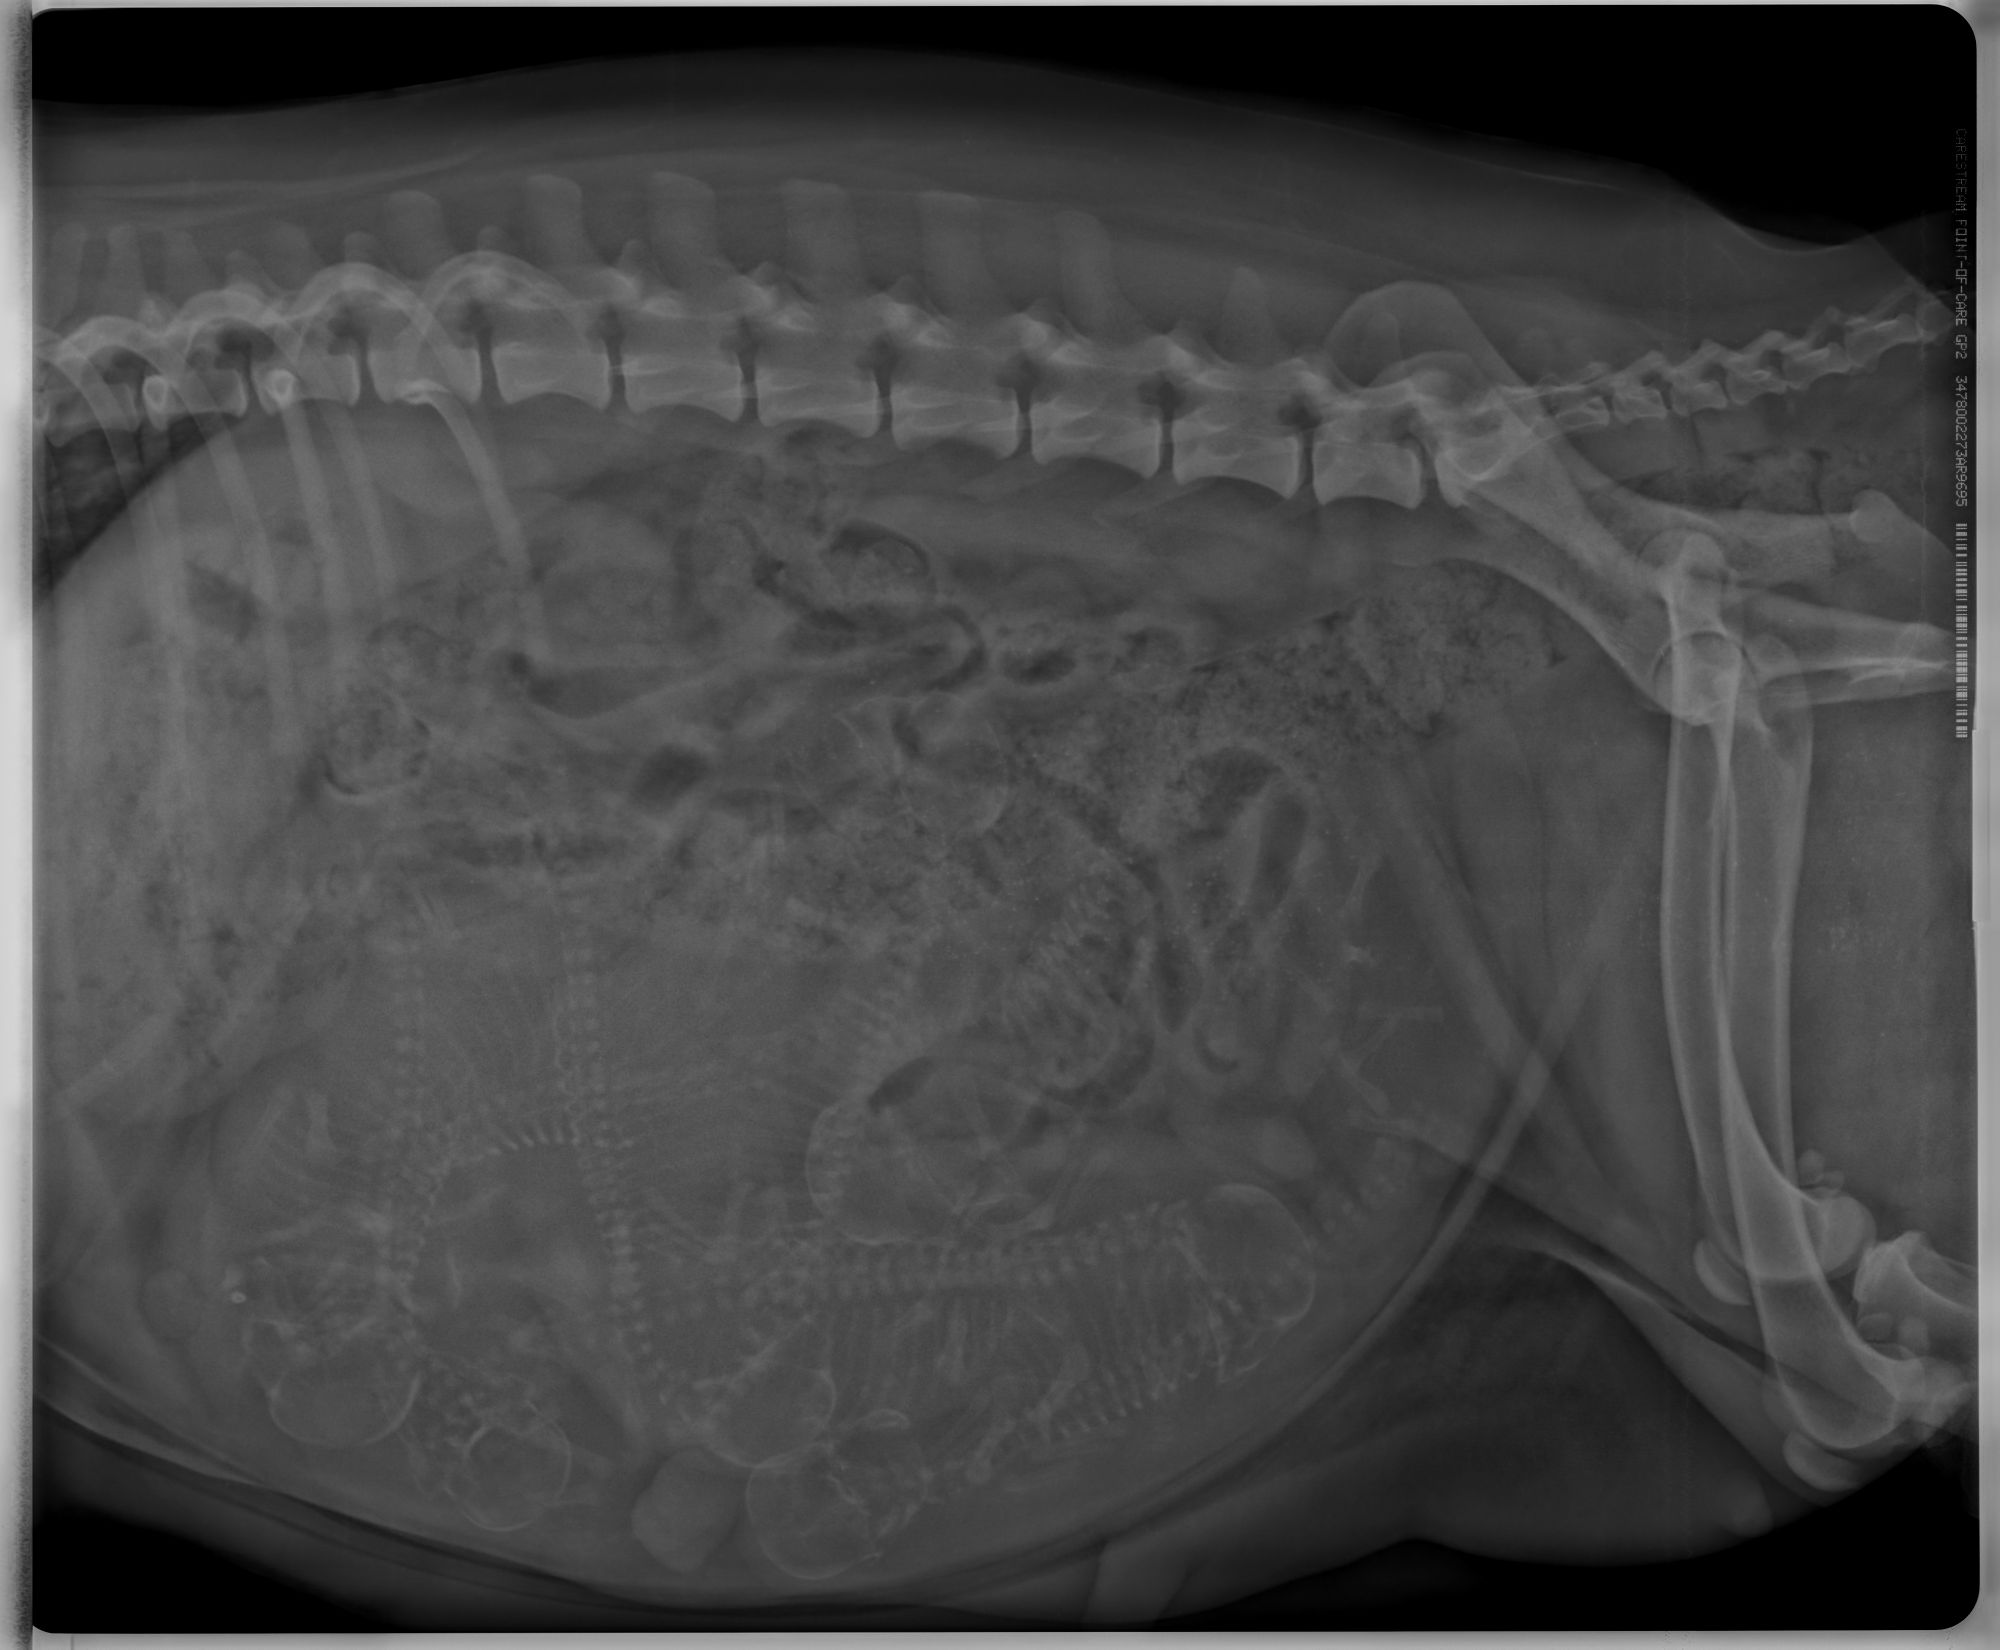

So nun die Innenaufnahme von Emmas Bauch. Einmal normal und einmal etwas bearbeitet und eingezeichnet. was wir gesehen haben. Also wer auf 7 gekommen ist beim zählen war sehr gut. Obwohl die Tierärztin einen 8. bei dem Knochensalat nicht ausschließen will. Dazu wollte Emma an den morgen auch absolut nicht kacken. Wir waren gleich früh um 8 Uhr dran, wir sind nach dem Röntgen dann aus der Praxis und Emma hat erstmal einen großen Haufen vor dem Fenster der Praxis gemacht, ob sie der Tierärztin damit was sagen wollte? Aber eine zweite Aufnahme wollten wir dann auch nicht mehr machen. Die Bauchzwerge sind alle ziemlich gleichmäßig entwickelt. Und von der Größe her dürfte es keine Probleme bei der Geburt geben, die Köpfe sind im Vergleich zum Becken nicht sehr groß. Aber die Größe ist halt nur ein Aspekt, der andere ist die Lage und leider können sie sich auch gegenseitig behindert bei der Geburt, aber wir hoffen nun alle das Beste. Emma wird froh sein, wenn die Welpen endlich da sind, die Wärme macht ihr teilweise schon ziemlich zu schaffen, sie liegt am liebsten da wo es kühl ist. Sie mag auch vom Nervzwerg Hexe nicht mehr allzuviel wissen. Momentan muss da Kiwi mehr erhalten. Ansonsten warten wir jetzt der Dinge die da kommen werden.

Ich war heute mit Emma beim Röntgen, leider hat mir die Tierärztin bisher das Bild nicht geschickt und ich will Euch den Spaß nicht nehmen selbst zu suchen. Daher gibt es noch keine Auflösung wieviele Welpen Emma bekommt.

Emma hat bisher 4,5kg zugenommen, noch ist etwa 1 Woche bis zur Geburt. Man sagt dass, die Mutterhündin für jeden Welpe bis zur Geburt circa 600-800g zunimmt. Und ich denke mal ein paar Gramm wird sie auch noch draufpacken... Wer gut in Mathe ist kann ja vielleicht auch schon errechnen wieviele es sind. ;) Obwohl 100% sicher waren wir uns beim Röngten auch nicht. Emma wollte vor dem Röngten partout nicht kacken.